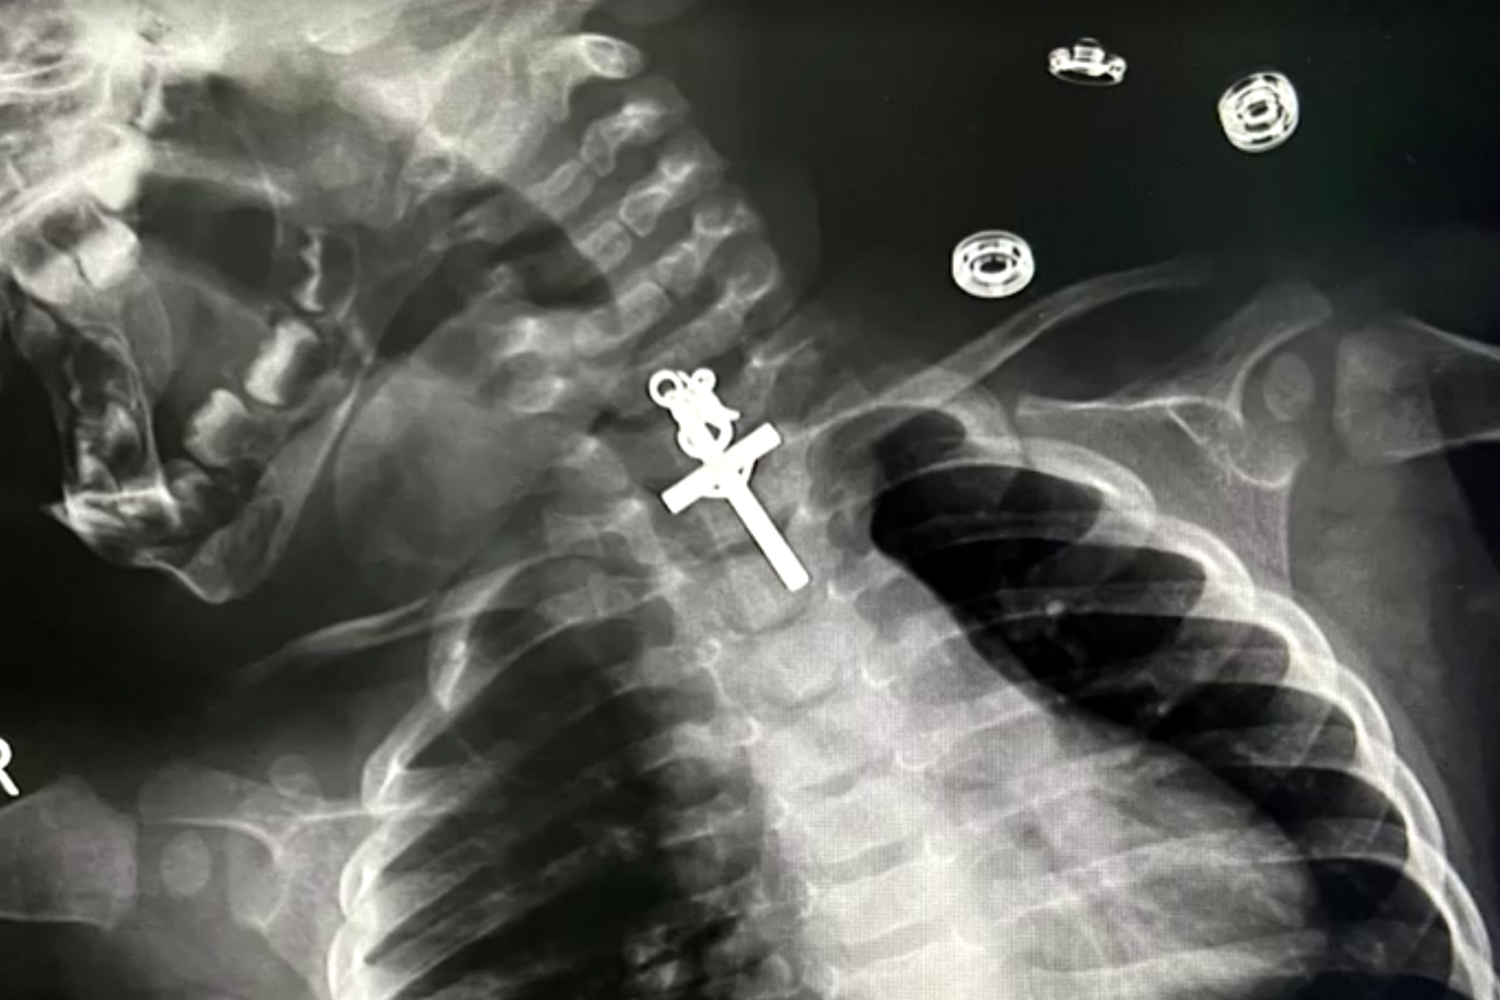

Os médicos do Hospital Víctor Lazarte, em La Libertad, no Perú, depararam-se com uma situação peculiar. Uma bebé de dez meses entrou na unidade de saúde com queixas graves e depois de realizar um raio-x foi detetado um crucifixo de metal alojado no esófago.

A equipa de profissionais de saúde conseguiu remover com sucesso o objeto. A operação foi um grande desafio para os médicos que tiveram de usar um endoscópio e pinças especiais, revela o Canal N

"O procedimento foi muito complicado porque o crucifixo estava alojado na parte superior do esófago. As primeiras tentativas de removê-lo não tiveram sucesso, porque estava preso. Tentámos várias vezes até conseguir", revela Luis Esteves Cabanillas, médico responsável pela operação, citado pela Reuters.